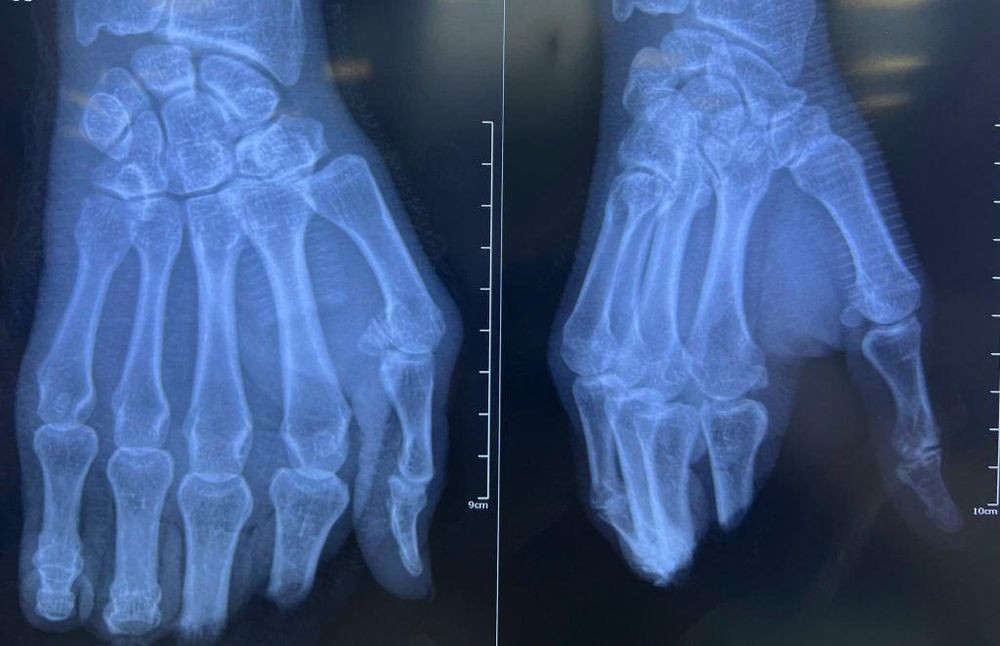

Hình chụp X-Quang bàn tay bị đứt lìa 4 ngón của người bệnh. (Ảnh: BVCC)

Bệnh nhân L.C.Q (64 tuổi) được đưa đến Bệnh viện Nhân dân 115 (TP.HCM) trong tình trạng đứt lìa các ngón II, III, IV, V bàn tay phải. Qua thăm khám, bác sĩ xác định đây là ca bệnh phức tạp do vị trí đứt tại khớp liên đốt gần và đốt xa, mô mềm dập nát nghiêm trọng. Đặc biệt, bệnh nhân lớn tuổi và có tiền sử hút thuốc lá lâu năm, làm tăng cao nguy cơ tắc mạch sau nối.

Ê-kíp phẫu thuật thực hiện kỹ thuật vi phẫu trong suốt 8 giờ liên tục để nối lại 4 ngón tay. Quá trình phẫu thuật bao gồm cố định lại xương, nối mạch máu, thần kinh và nối gân gấp duỗi từng ngón tay.